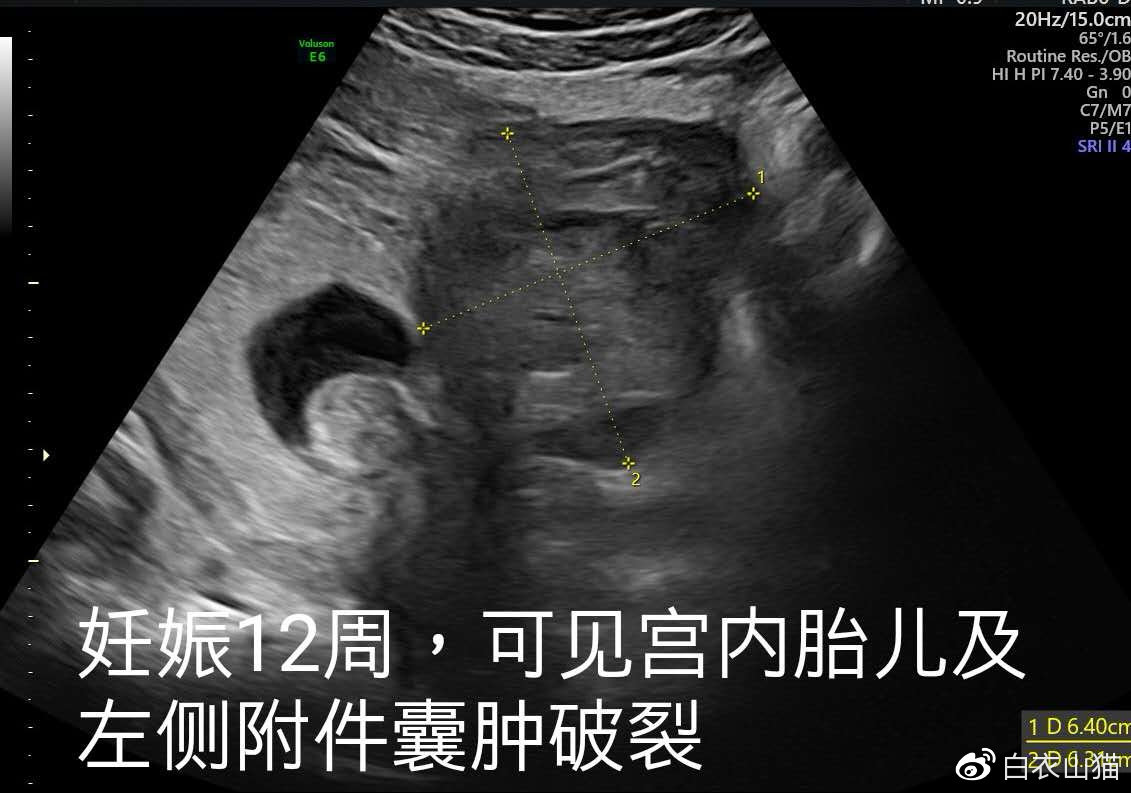

双胞胎一个宫内一个宫外大出血,双胞胎一个流产一个宫外孕

最后一次B超,发现左侧附件囊肿破裂。

小兰的腹痛慢慢缓解,昨天,她要求出院了。医生不放心,再次给她做了B超。这个时候,发现了小兰左侧的囊肿好像破了。